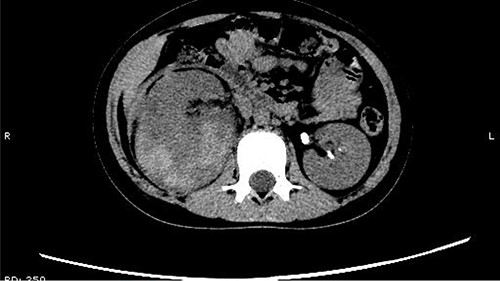

The patient was confined to bed, fasted and prescribed a daily intravenous infusion of cefazolin sodium pentahydrate, 2.0 g for 10 days. CT showed some irregular high-density shadows were present in the left renal pelvis (Fig. 1), and a small strip of high-density shadow was apparent in the bladder cavity (Fig. 2). Blood tests showed no abnormality in serum calcium concentration. Cefazolin sodium pentahydrate was discontinued immediately.

Some irregular high-density shadows was present in the left renal pelvis.